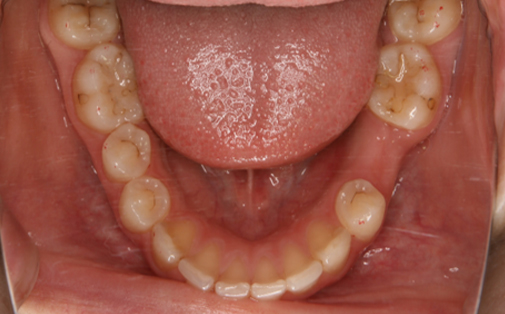

Before

After

左下の親知らずの歯を移植の症例です。